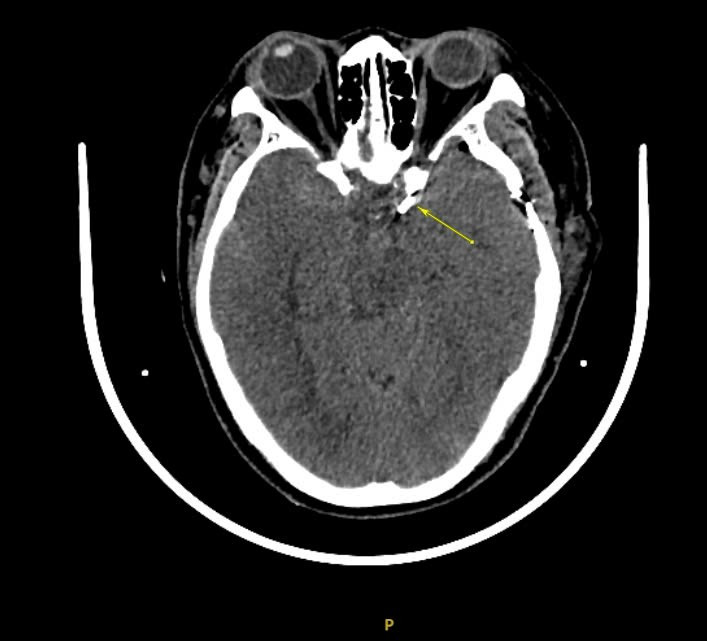

Bệnh nhân được nhanh chóng chụp CT mạch máu não ghi nhận xuất huyết khoang dưới nhện bể trước cầu não, rãnh Sylvian, xuất huyết não thất hai bên do vỡ túi phình động mạch cảnh trong đoạn thông sau bên trái.

| Vỡ túi phình trên phim chụp - Ảnh BVCC |